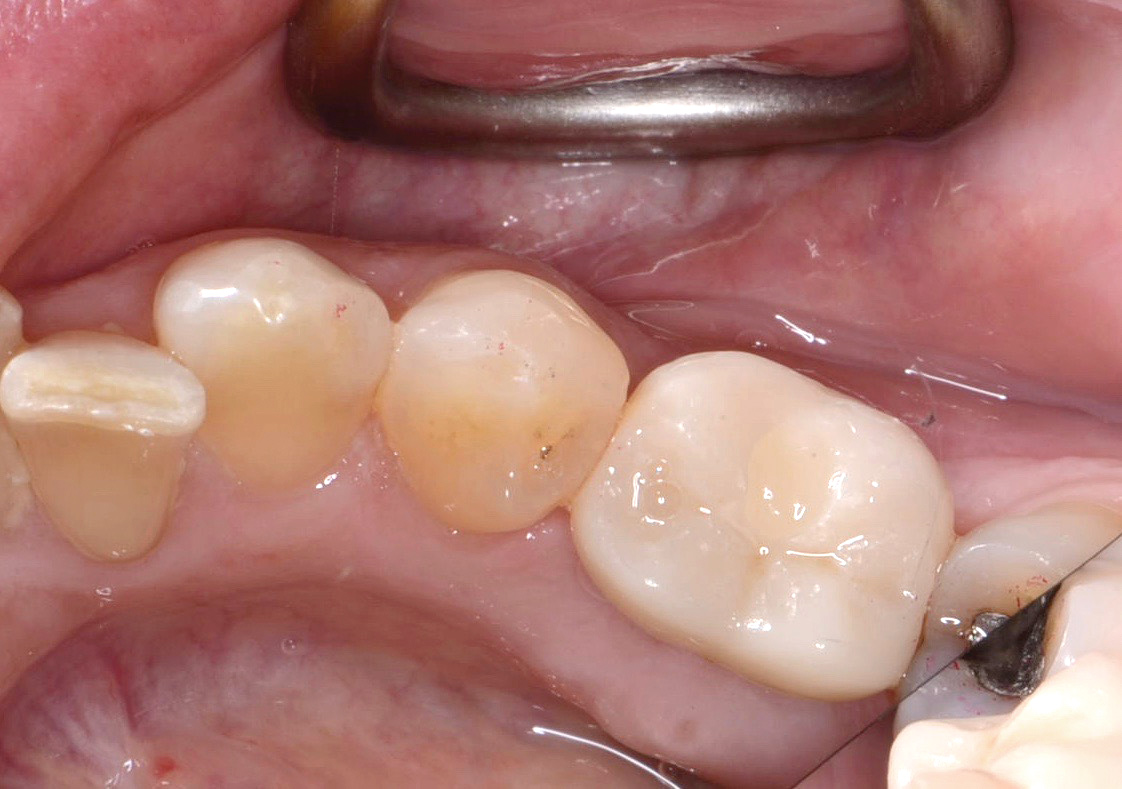

Fig 15. Implant abutment following cement removal.

Figure 15

If all implant-supported crowns could be designed for screw retention, no discussion of excess cement would be necessary. However, screw retention is not always possible depending on the location of the access opening and because of the unesthetic appearance in anterior restorations or the mesial/distal angulation of the implant compromising the path of insertion (Figure 12). Residual cement left after crown cementation on implants can lead to peri-implant inflammation, peri-implantitis, and eventual loss of the implant (Figure 13 through Figure 15).25 The presence of lingering excess cement can encourage the development of bacterial colonization and peri-implantitis. Conversely, when too little cement is used, voids in the cement layer can occur and the prosthesis can become loose.26 The deeper the implant crown margin, the more difficult it is to remove excess cement.27

Radiopaque cements that contain zinc phosphate and zinc oxide (with and without eugenol) should be considered to help identify excess interproximal cement; however, this should be used secondarily to proper margin height and careful removal of cement during cementation. Resin cements lack the same opacity as zinc-containing cements and have been shown to be the most difficult to remove.28 Often in the process of removing this excess cement, the abutment surface becomes scratched and damaged, potentiating further plaque accumulation.29

Several modifications in abutment design and cementation have been suggested. Placing vent holes in the abutment during fabrication or leaving most of the screw-access chamber open for access has reduced the amount of cement that expresses out into the sulcus.26 It is also beneficial to extraorally express excess cement on an abutment replica prior to final crown seating to minimize complications. If retrievability is desired with cementable implant crowns, weaker cements (eg, zinc oxide eugenol) should be used first and progressively changed until the desired retention is achieved.